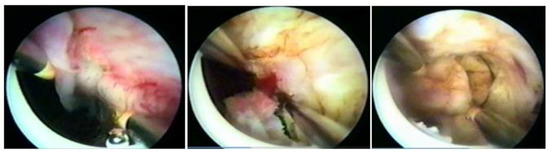

Myomectomy, whether laparotomic or laparoscopic, is a well-established procedure, widely performed with the goal of uterine preservation. In both approaches, the myomectomy technique is the same: incision of the serosa up to the pseudocapsule, identification of the myoma, traction and movement of the nodule, assistance in dissecting the plane of the pseudocapsule within the myometrium, and enucleation of the myoma from the uterine wall. This fibroid enucleation technique is known and performed by all gynecologists. When the pseudocapsule is reached, the chance of preserving the uterus will be greater, with less bleeding and less myometrial damage, which differs from adenomyosis resection, which does not have a pseudocapsule [21] (Figure 6).

Figure 6. Laparotomic and laparoscopic myomectomy preserving pseudocapsule.